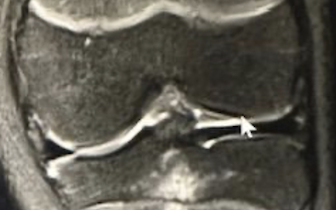

The Extremities

Differential Diagnosis